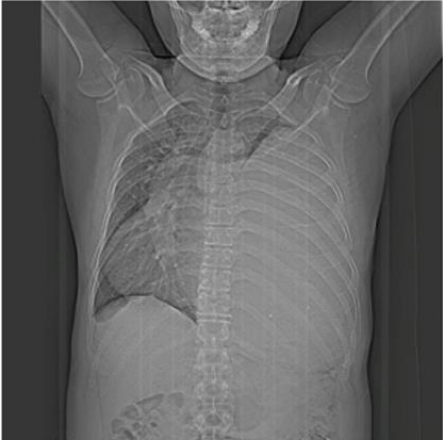

The case of a 47-year-old male patient is presented. He was admitted to the emergency room with a clinical picture of 6 months' evolution given by respiratory symptoms of NYHA III type dyspnea, adynamia, asthenia, and mild pain in the left costal grid. He did not report any important or relevant history for the case. Upon admission to the service, a chest x-ray was requested, which showed great left opacity with displacement of the trachea and cardiac silhouette; the left lung is not visualized.

Image 1: Chest X-ray